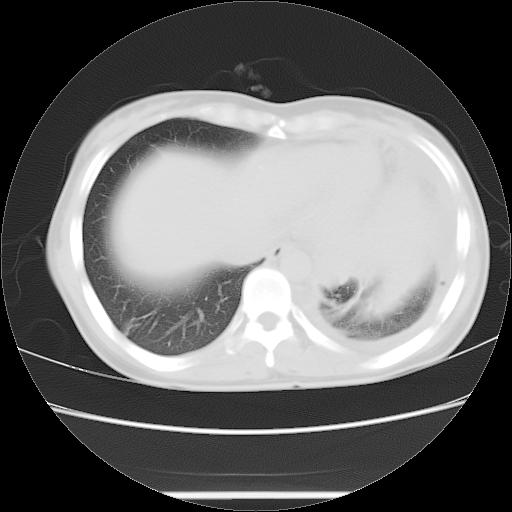

女,29岁,胸部不适,在外院胸片提示胸腔积液,到我院ct检查。

1、左侧包裹性积液伴叶间积液 2、右肺多发结节考虑增殖结节

左侧纵隔胸膜包裹性积液、左侧胸腔积液、胸膜肥厚粘莲,考虑结核性胸膜炎

左肺上叶不张,左侧胸水,叶间裂积液,纵隔淋巴结,脾脏钙化,考虑左肺上叶支气管内膜结核,结核性胸膜炎,脾结核

考虑:1.两肺tb;2.左侧胸膜炎、胸腔积液。

考虑两肺结核,左侧包裹性积液,叶间积液。

支持两肺继发性肺结核,左侧胸膜腔包裹性积液、胸膜肥厚,脾内多发钙化(结核钙化)。